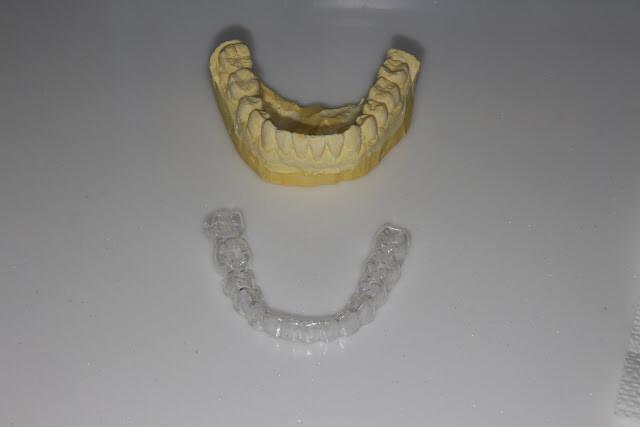

透明維持器(clear overlay)與石膏模型分離,跟隱形牙套很像吧,兩者工序很像,只是材質不同

透明維持器(clear overlay),跟隱形牙套很像吧